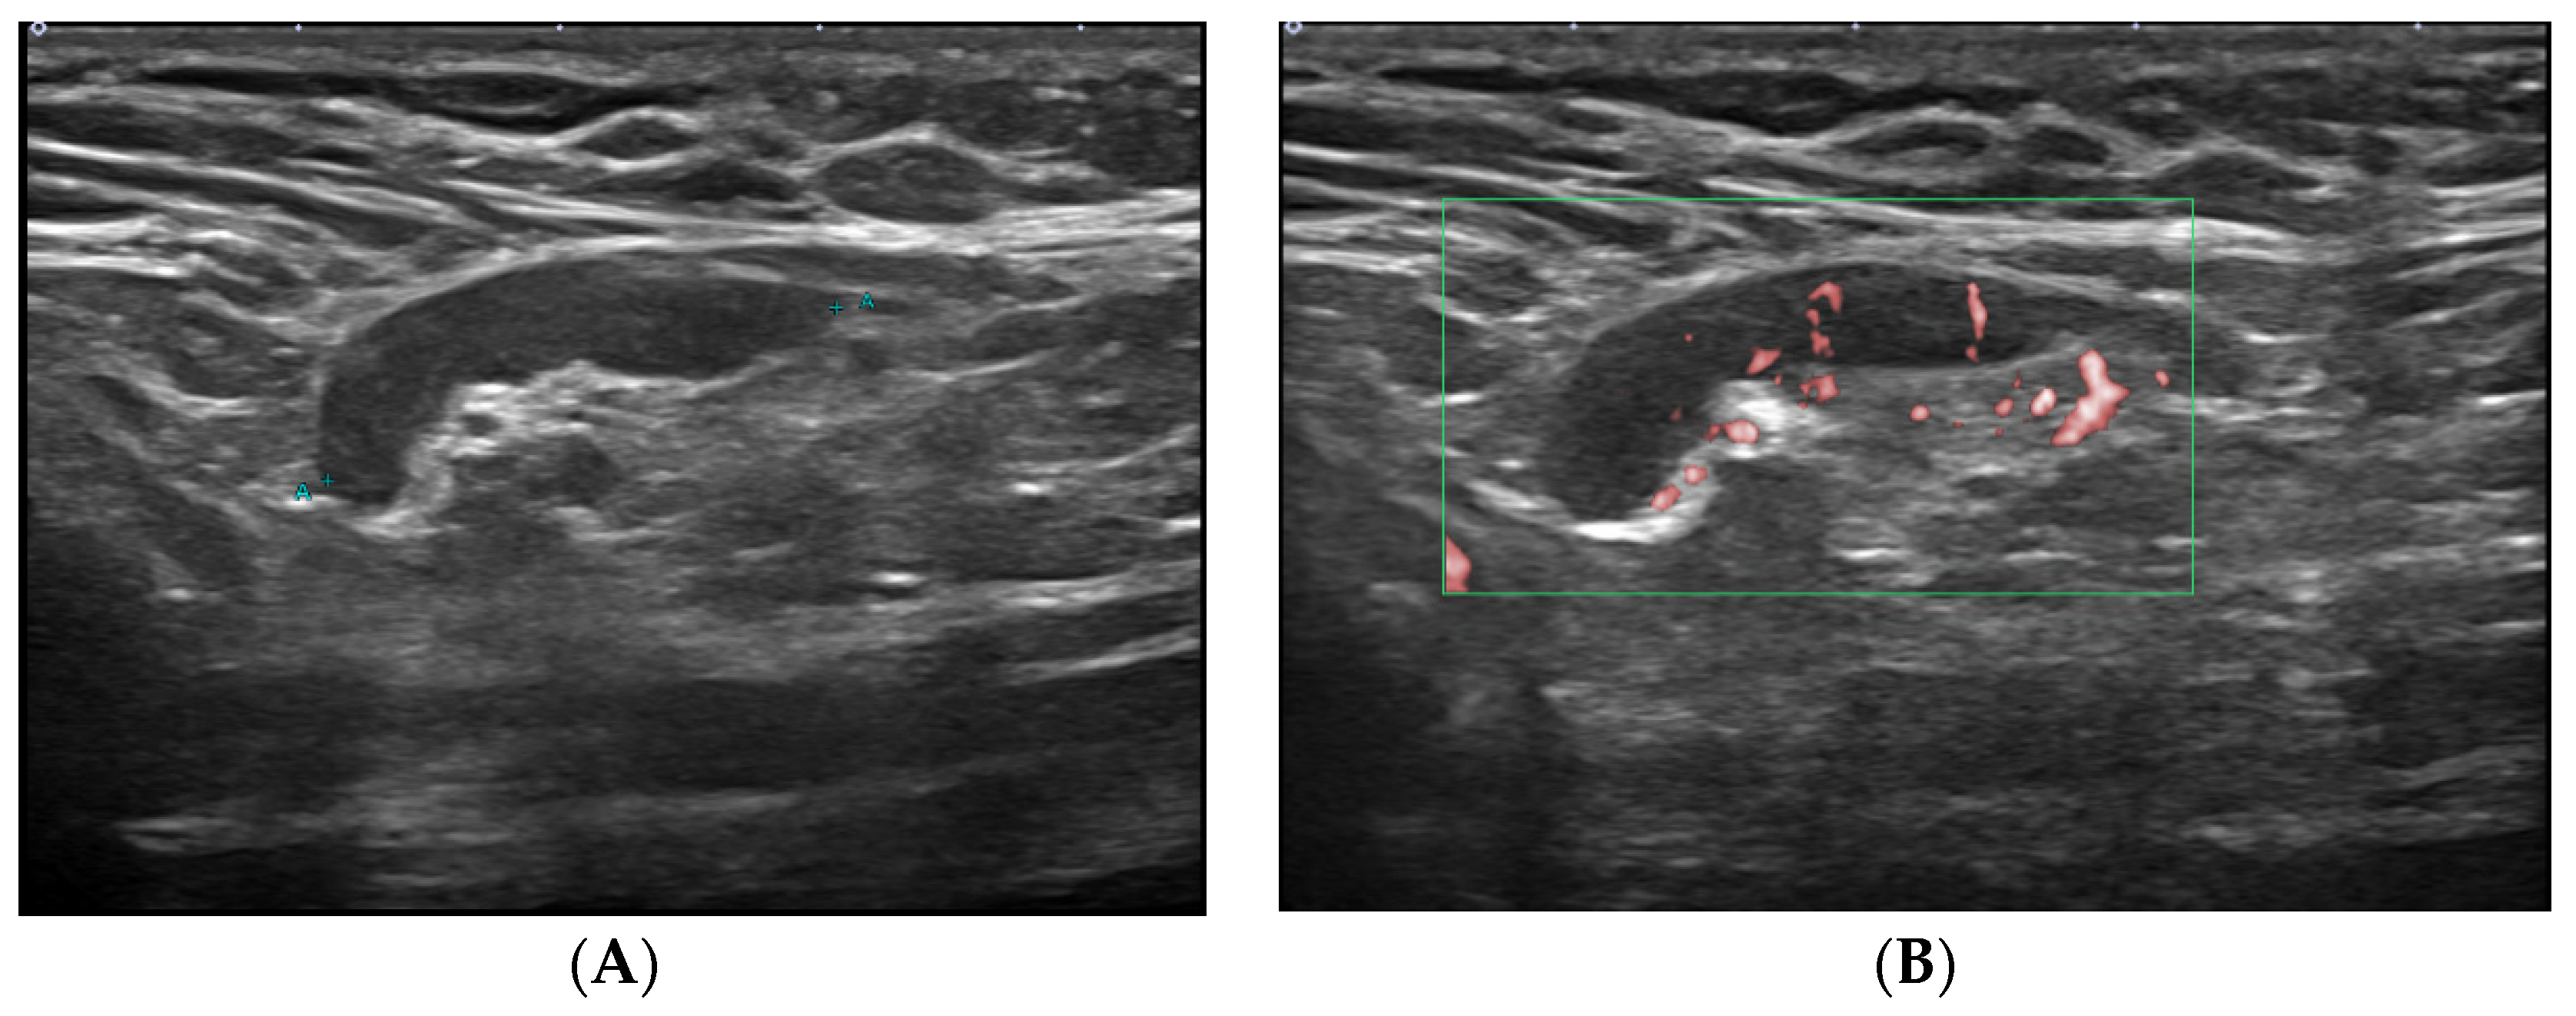

2.2. Ultrasound Technique

- Cocco, G.; Delli Pizzi, A.; Fabiani, S.; Cocco, N.; Boccatonda, A.; Frisone, A.; Scarano, S.; Shiavone, C. Lymphadenopathy after the anti-COVID-19 Vaccine: Multiparametric ultrasound findings. Biology 2021, 10, 652. [Google Scholar] [CrossRef]

- Granata, V.; Fusco, R.; Setola, S.V.; Galdiero, R.; Picone, C.; Izzo, F.; D’Aniello, R.; Miele, V.; Grassi, R.; Grassi, R.; et al. Lymphadenopathy after BNT162b2 Covid-19 vaccine: Preliminary ultrasound findings. Biology 2021, 10, 214. [Google Scholar] [CrossRef]